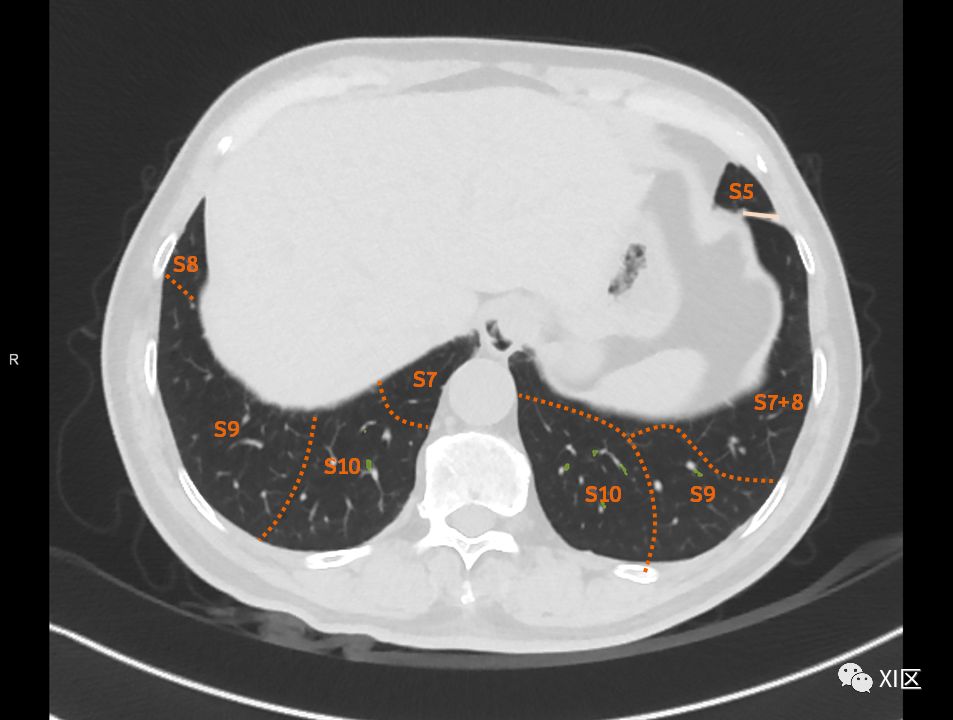

在进行肺的分段时,可以上下观察浏览,沿着相应气管的走形可以更容易准确地进行分段。

肺的断层分段示意图